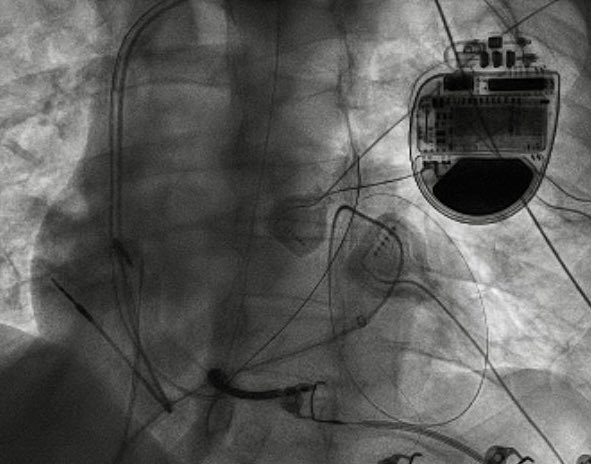

@drjefflin Micra AV placed for CHB 3 months ago. In clinic, pt noted fatigue and found to have sinus node dysfunction. Symptoms thought to be due to dyssynchrony with V pacing. Transvenous DC-PPM placed and pt wished to have leadless ppm removed.